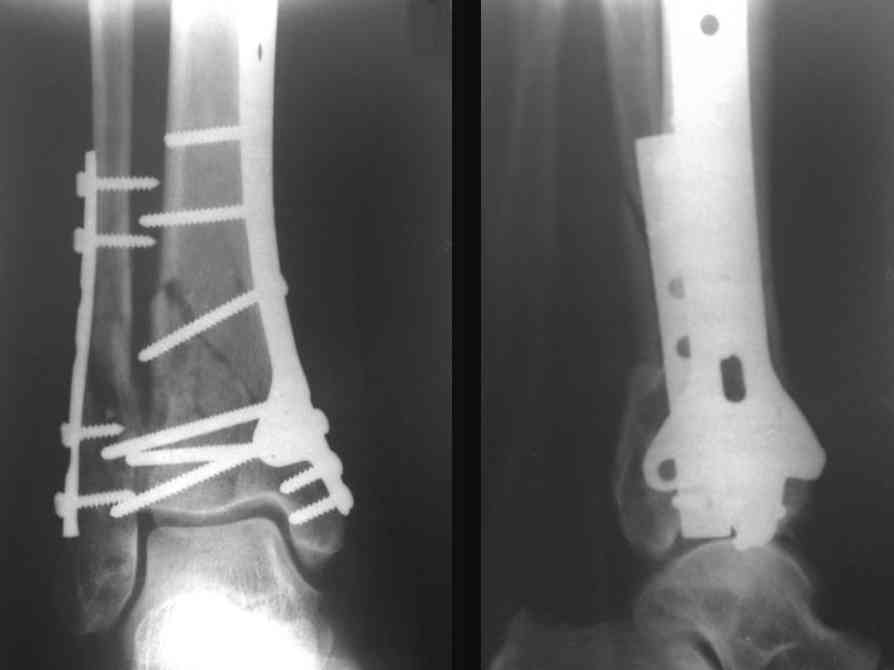

Посылаю результат лечения предыдущего больного через год.

С уважением Дрягин